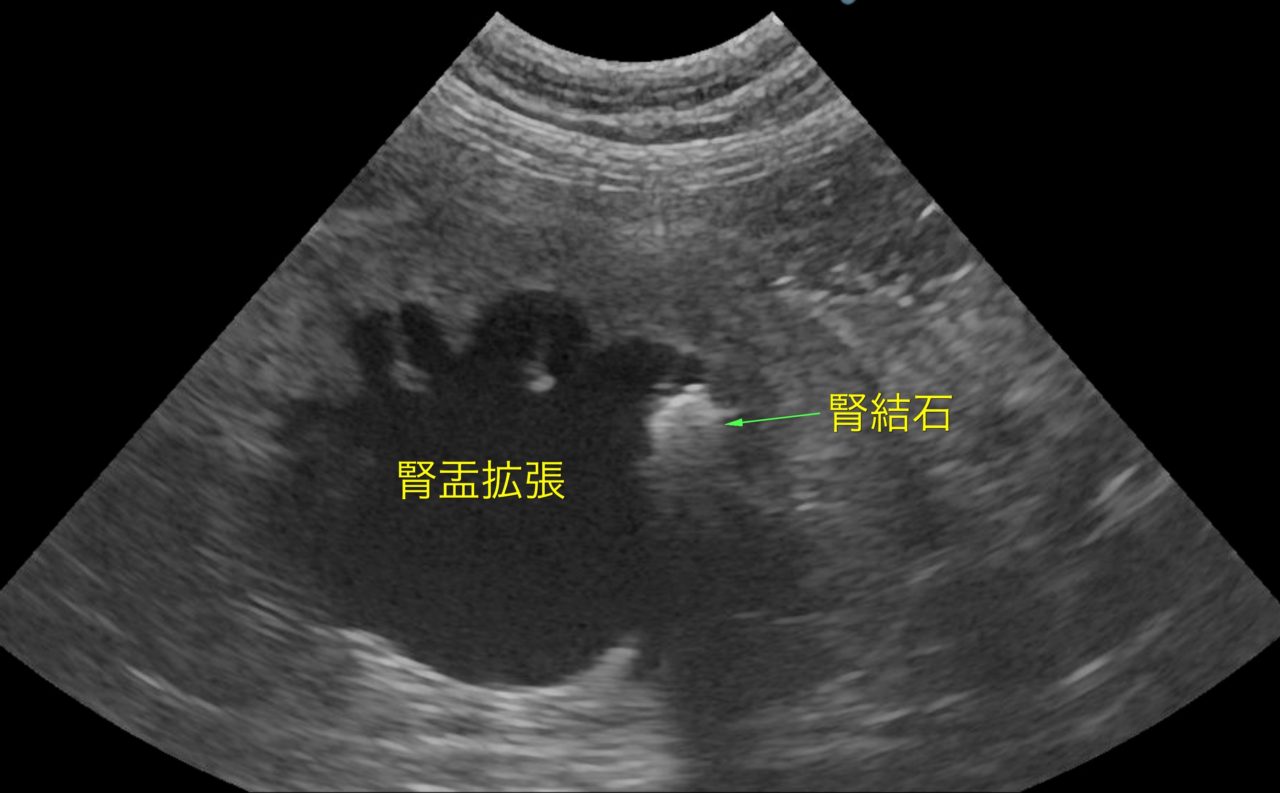

腎結石(尿管結石)|猫の病気|動物の病気|あいむ動物病院 西船橋

猫の尿管結石 動物の腎臓病 どうぶつ腎臓病センター